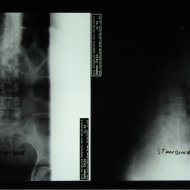

Bel kayması olan hastanın ameliyat öncesi ve sonrası röntgeni